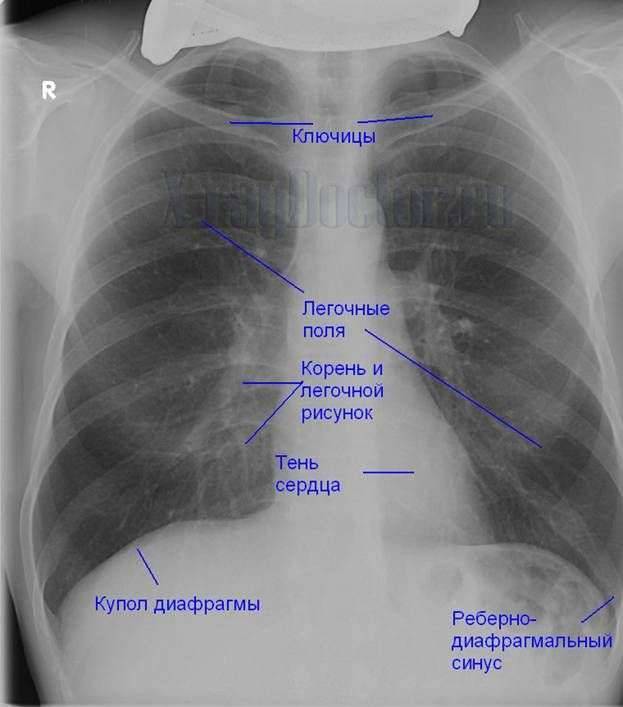

Рентген здоровых легких: примеры снимков и советы

Раздел: Сокровищница опыта